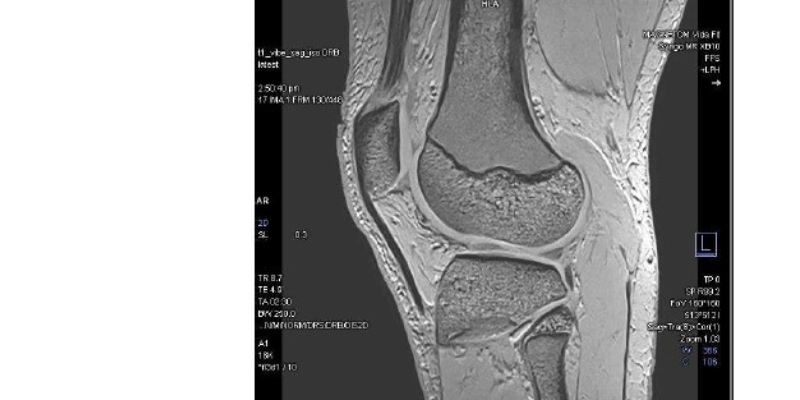

The MAGNETOM Vida Fit also brings advanced AI-driven imaging and a patient-friendly design, offering exceptional diagnostic capabilities across neurology, oncology, musculoskeletal, and cardiovascular care. Features such as BioMatrix and Deep Resolve ensure consistent, high-quality results with reduced scan times, whilst the latest coil technology enhances patient comfort.